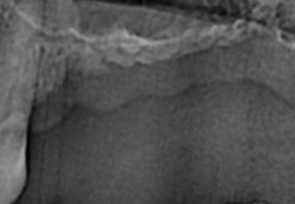

before

-

after